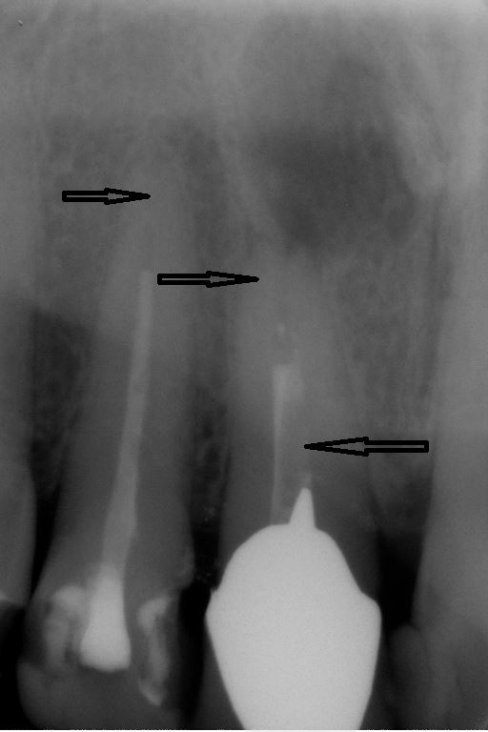

Fallbeispiel für einen komplexen Kanalverlauf

Da die Wurzelkanäle sehr klein sind und sich oft verzweigen, ist es nicht immer einfach, alle Kanäle mit ihren Seitenästen aufzufinden.

Bei der modernen endodontischen Behandlung können durch ein Dentalmikroskop auch kleinere Kanälchen aufbereitet werden, die man auch mit einer Lupenbrille nicht finden würde.

Nur wenn das Wurzelkanalsystem komplett aufgefunden und gereinigt wird, hat eine Wurzelkanalfüllung eine gute Langzeitprognose.